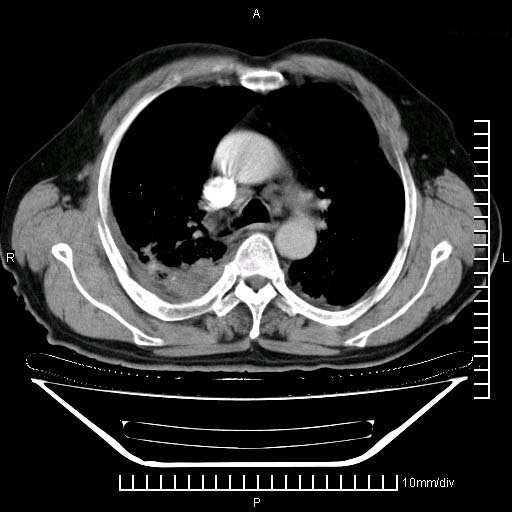

既往肺结核,近10几天,咳嗽,咳痰,右侧胸痛,疼痛较明显,右上肺斑块考虑结核灶胸膜粘连,增强,可惜动脉期没有定好,未见强化,可延迟4分后又见较明显强化,中心见低密度影,如果说结核是边缘强化,可这个灶强化的面积挺大的,让人很挠头。

动脉期